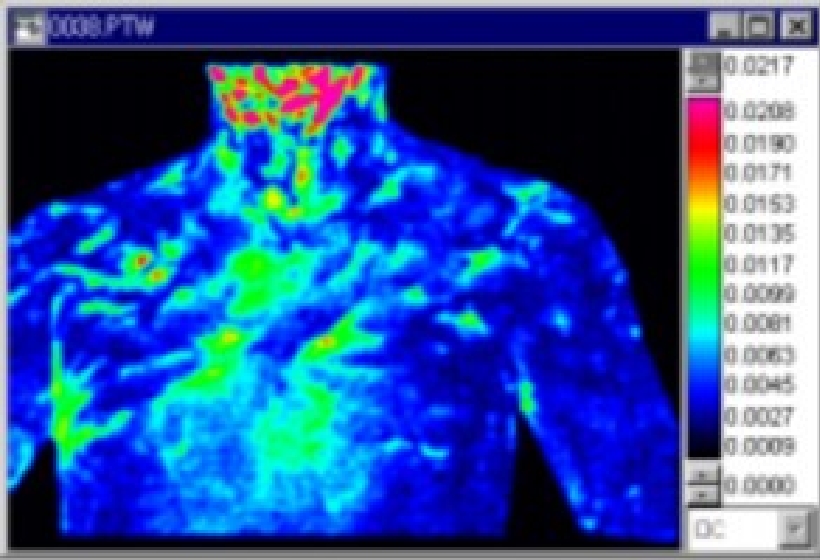

生体観察

サーモグラフィの代表的な用途として生体の温度観測がある。しかしながら現在主流の生体用赤外線カメラの温度分解能は0.1-0.05℃と低い。そこで更なる温度分解能の向上とロックイン方式による観測を行うと、心臓の鼓動に応じた体表面の温度変化画像を測定することが可能となる。ここでは、心拍数72回(1.2Hz)としてロックイン方式で赤外線温度差画像を撮影した。図10に人体表面の赤外線温度画像、図11にロックイン方式による赤外線温度差画像を示す。